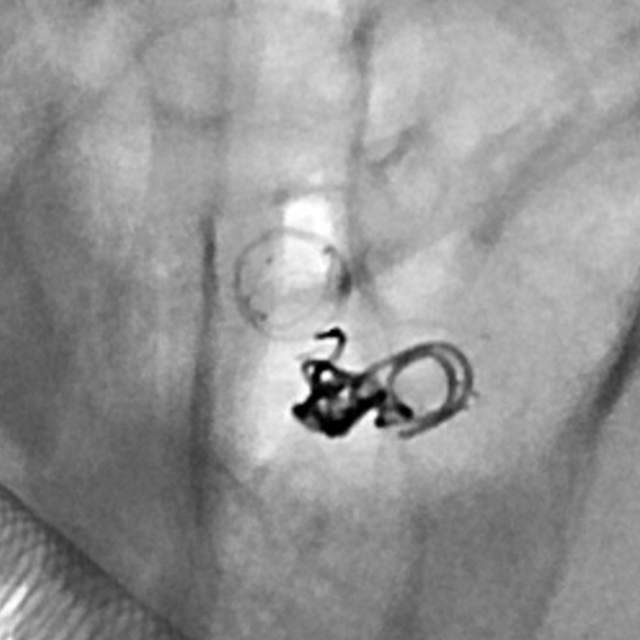

病情变化:中年男性患者,由于头晕查体发现后交通动脉瘤,第一次造影可见形态尚规则,患者及家属经过反反复复的思想斗争,决定采用外科干预。3天后,术中发现动脉瘤的形态已经出现改变,瘤囊的远端出现子瘤。